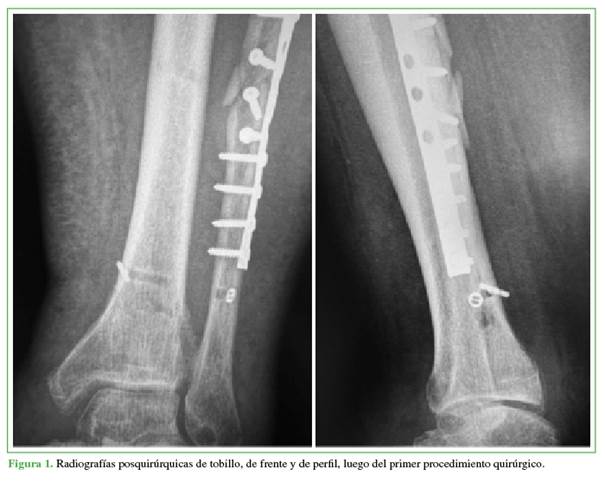

Hombre de 60 años, obeso (índice de masa corporal 35), sin antecedentes de relevancia. Había sufrido una caída desde su propia altura en su domicilio, que le provocó tumefacción y dolor en el tobillo derecho, por lo que concurre al Servicio de Urgencia donde se le tomaron radiografías de tobillo, de frente y perfil. El diagnóstico fue luxofractura de tobillo. Se le realizó una reducción, se le colocó una valva posterior de yeso y quedó hospitalizado. A las 24 h, fue sometido a una reducción y osteosíntesis con tornillos interfragmentarios y placa de neutralización en el peroné y fijación de la sindesmosis con Endobutton® por fuera de la placa (Figura 1).